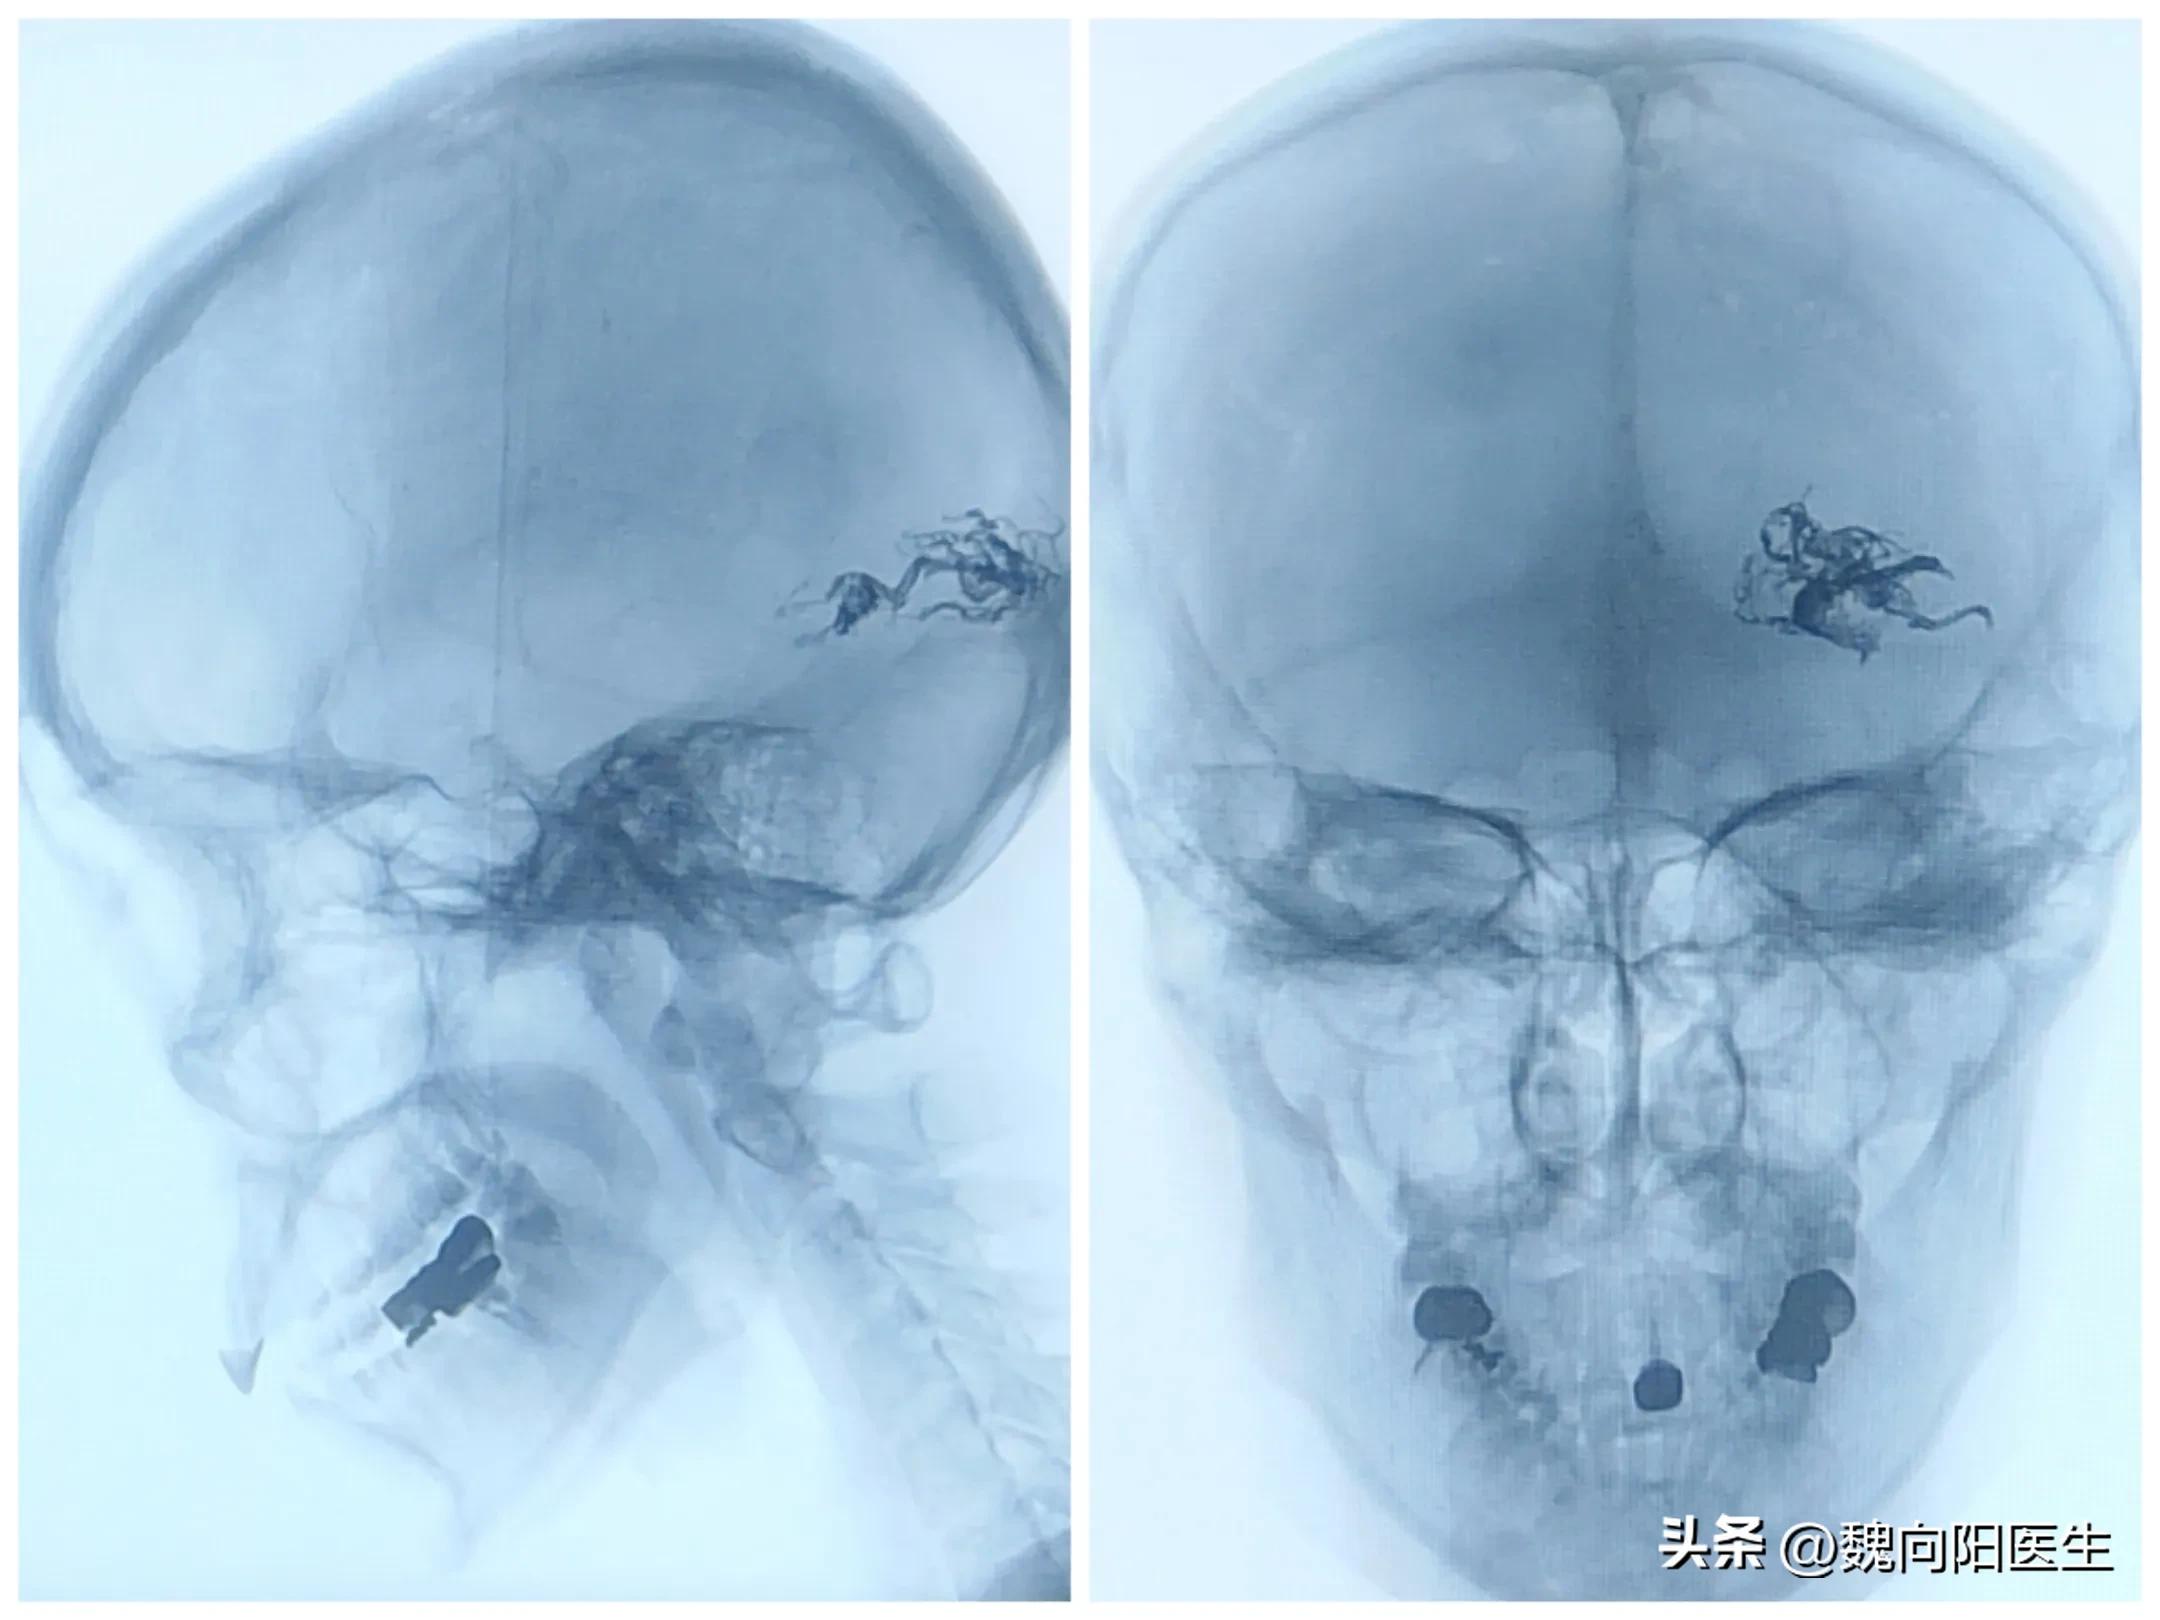

当脑血管造影做完之后,发现是左侧枕叶血管畸形。经与患者家属充分沟通之后,决定采取介入手术治疗,立即给患者行经导管动静脉畸形栓塞术。

且病根是脑血管畸形,很容易会导致再次出血,此次手术只是栓塞了一部分血管,并没有完全治愈。

@魏向阳医生对于严重的血管畸形,往往需要分期手术治疗,每次栓塞一部分畸形血管。如果一次全部栓塞会导致脑血容量负荷积极增加,会增加脑出血的风险。

半年后,患者又做了一次栓塞和脑伽玛刀治疗,基本上每两年患者就会过来复诊一次,这次已经是第4次复诊。